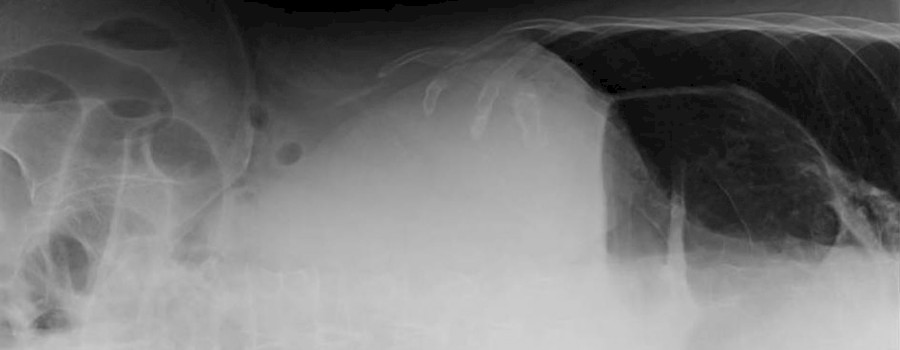

Beim "Thorax-Magen" bzw "upside-down-Magen" kommt es durch einen großen Zwerchfellbruch zu einem teilweisen oder kompletten Hochgleiten des Magens in die Brusthöhle. Dies ist häufig begleitet von Herz-/Kreislaufbeschwerden, Atemnot, Völlegefühl und Blutarmut.